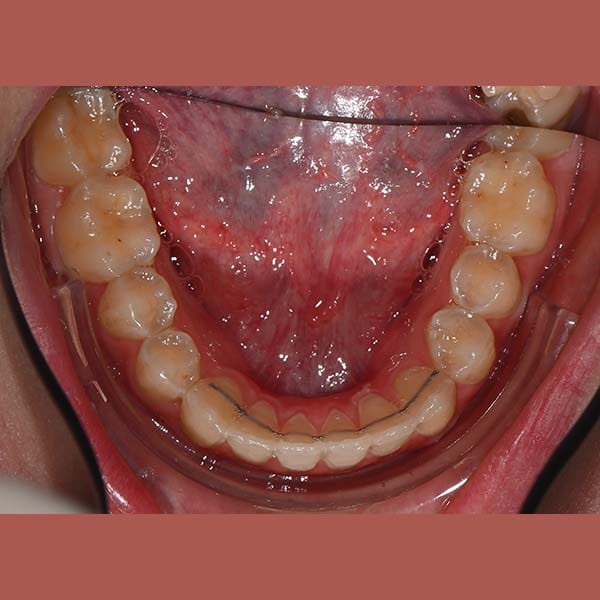

BEFORE

Our young reviewer asked me to treat the simple overlay in her front upper and lower teeth, but she didn’t want anyone to notice her braces. The ideal solution was the invisible braces from Invisalign. After a few months of treatment, all of her teeth were beautifully aligned, and most importantly, no one noticed that she was wearing braces.